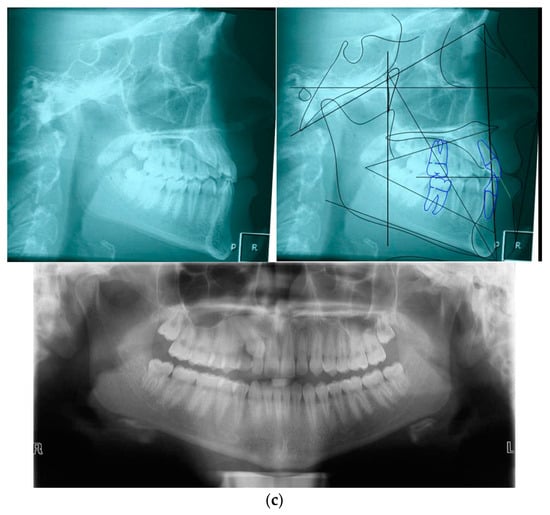

| Sagittal Jaw Relationship | ||

|---|---|---|

| Patient Value | Normal Value | |

| Maxillary position SNA (°) | 81.4 | 82 ± 3.5 |

| Mandibular position SNB (°) | 81.8 | 80 ± 2.5 |

| Sagittal jaw relation ANPg (°) | −0.4 | 2 ± 2.5 |

| Vertical jaw relationship | ||

| Maxillary inclination SN^ANS-PNS (°) | 5.7 | 8 ± 3 |

| Mandibular inclination SN^GoGn (°) | 28.4 | 33 ± 2.5 |

| Vertical jaw relation ANS/PNS^GoGn (°) | 25.5 | 25 ± 6 |

| Dento-basal relationship | ||

| Maxillary incisor inclination U1^ANS-PNS (°) | 111.9 | 110 ± 6 |

| Mandibular incisor inclination L1^GoGn (°) | 81.8 | 94 ± 7 |

| Mandibular incisor compensation (L1-Apo) (mm) | 1.5 | 2 ± 2 |

| Dental relationship | ||

| Overjet (mm) | 2.9 | 3.5 ± 2.5 |

| Overbite (mm) | 2.1 | 2.5 ± 2.5 |

| Interincisal angle (°) | 143.5 | 132 ± 6 |